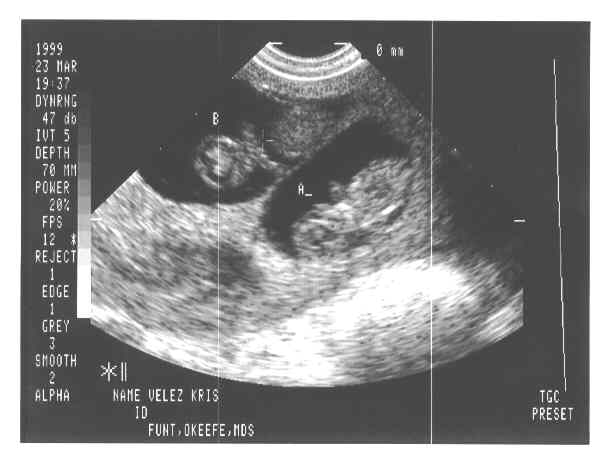

eggs2.JPG - 19.8 K eggs3.JPG - 22.4 K eggs4.JPG - 11.7 K babies-1a.JPG - 21.3 K